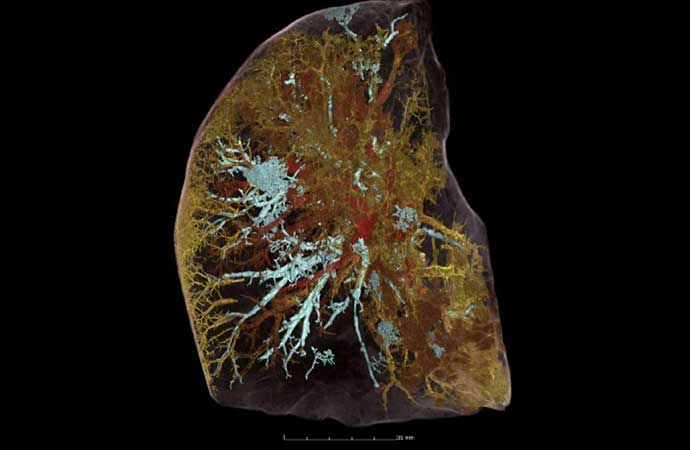

Легкие Ковид19 Фото

Легкие Ковид19 Фото 112 фотографий